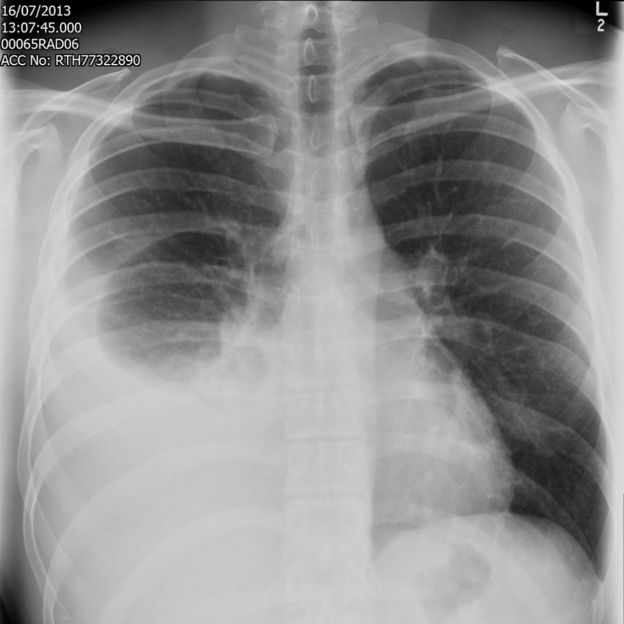

"My right lung was virtually non-existent - they drained 2.5 litres of

fluid from my right pleural space [the area around the lungs]," Jonathan

said.